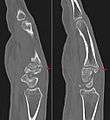

| Carpal boss in plain X-Ray. |

The joint between the index metacarpal and the capitate is a fibrous non-mobile joint. Some people have a gene that leads to this growth. It looks like arthritis (bone spurs on each side of the joint) on X-ray. It looks like a ganglion on the hand, but more towards the fingertips.

The carpometacarpal joint is usually found at the base of the second and third metacarpal bones at the point where they meet the small bones of the wrist.[2]